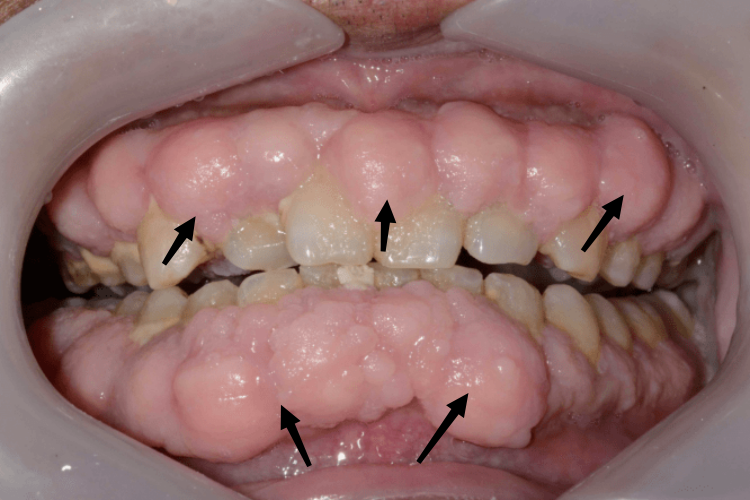

药物性牙龈肥大

药物性牙龈肥大的牙龈增生一般开始于服药后1~6个月,增生起始于唇颊侧或舌腭侧龈乳头,呈小球状突起于牙龈表面,增生牙龈基底与正常牙龈之间可有明显的沟状界线。增生牙龈可向边缘龈扩展,覆盖部分牙面。牙龈呈淡粉红色,质地坚韧,略有弹性,一般不易出血。无自觉症状,无疼痛。